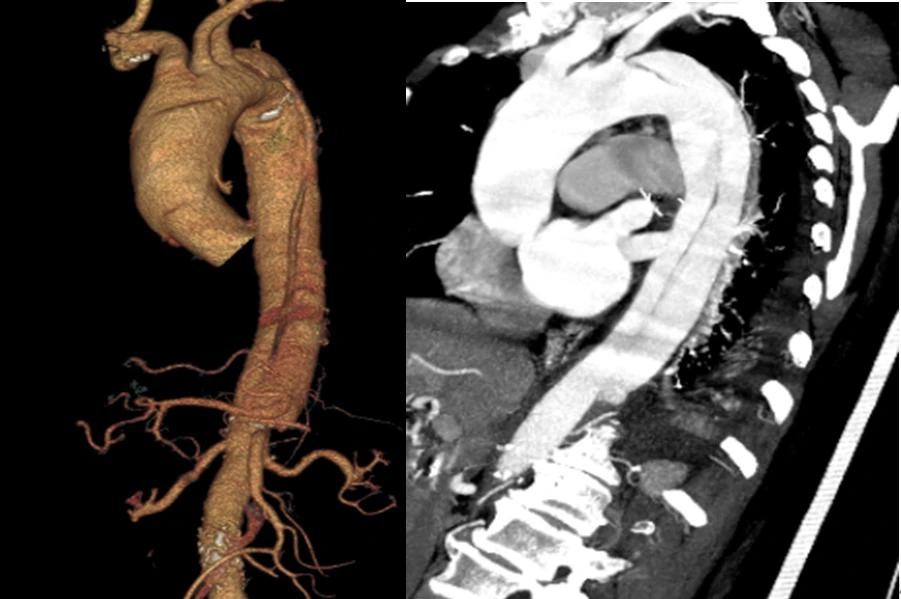

主动脉夹层

手术展示